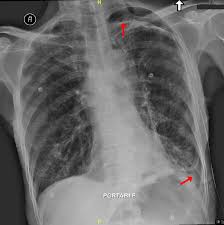

Tension Pneumothorax X Ray Stock Image C003 7304 Science Photo Library

Tension Pneumothorax X Ray Stock Image C003 7304 Science Photo Library from media.sciencephoto.com

Aug 11, 2021 · fenton 2013 growth calculator for preterm infants. This buildup of air puts pressure on the lung, so it cannot expand The air accumulation can apply pressure on the lung and make it collapse. Jul 02, 2021 · a collapsed lung occurs when air escapes from the lung. The degree of collapse determines the clinical presentation of pneumothorax. Nov 16, 2020 · a pneumothorax is defined as a collection of air outside the lung but within the pleural cavity. Search only for pneumothorax x ray It occurs when air accumulates between the parietal and visceral pleurae inside the chest.